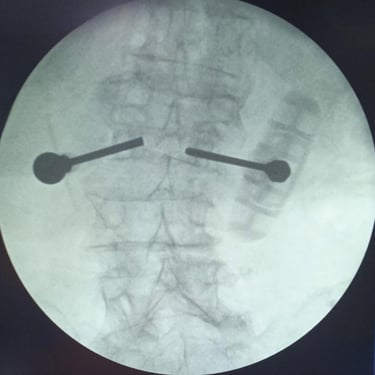

Fractura Lumbar Osteoporótica / Vertebroplastía y Bloqueo Lumbar Selectivo

La fractura lumbar osteoporótica y la artrosis lumbar son causas frecuentes de dolor crónico y limitación funcional en el adulto mayor. La osteoporosis debilita las vértebras, favoreciendo fracturas incluso ante esfuerzos mínimos, mientras que la artrosis genera desgaste articular e inflamación. La vertebroplastía percutánea permite estabilizar las vértebras fracturadas mediante la inyección de cemento óseo, proporcionando alivio rápido y mejorando la movilidad. En casos de dolor persistente por artrosis, el bloqueo lumbar selectivo ayuda a reducir la inflamación y el dolor. Ambas técnicas son procedimientos mínimamente invasivos que mejoran la calidad de vida y facilitan la recuperación funcional.